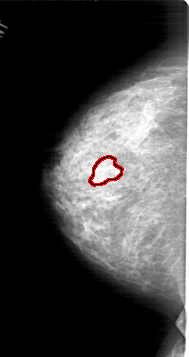

A_1453_1.LEFT_MLO

LEFT_MLO LINES 6076 PIXELS_PER_LINE 3526 BITS_PER_PIXEL 12 RESOLUTION 43.5 OVERLAY

FILE: A_1453_1.LEFT_MLO.OVERLAY

TOTAL_ABNORMALITIES 1

ABNORMALITY 1

LESION_TYPE MASS SHAPE LOBULATED MARGINS OBSCURED

ASSESSMENT 4

SUBTLETY 2

PATHOLOGY BENIGN

TOTAL_OUTLINES 1

BOUNDARY